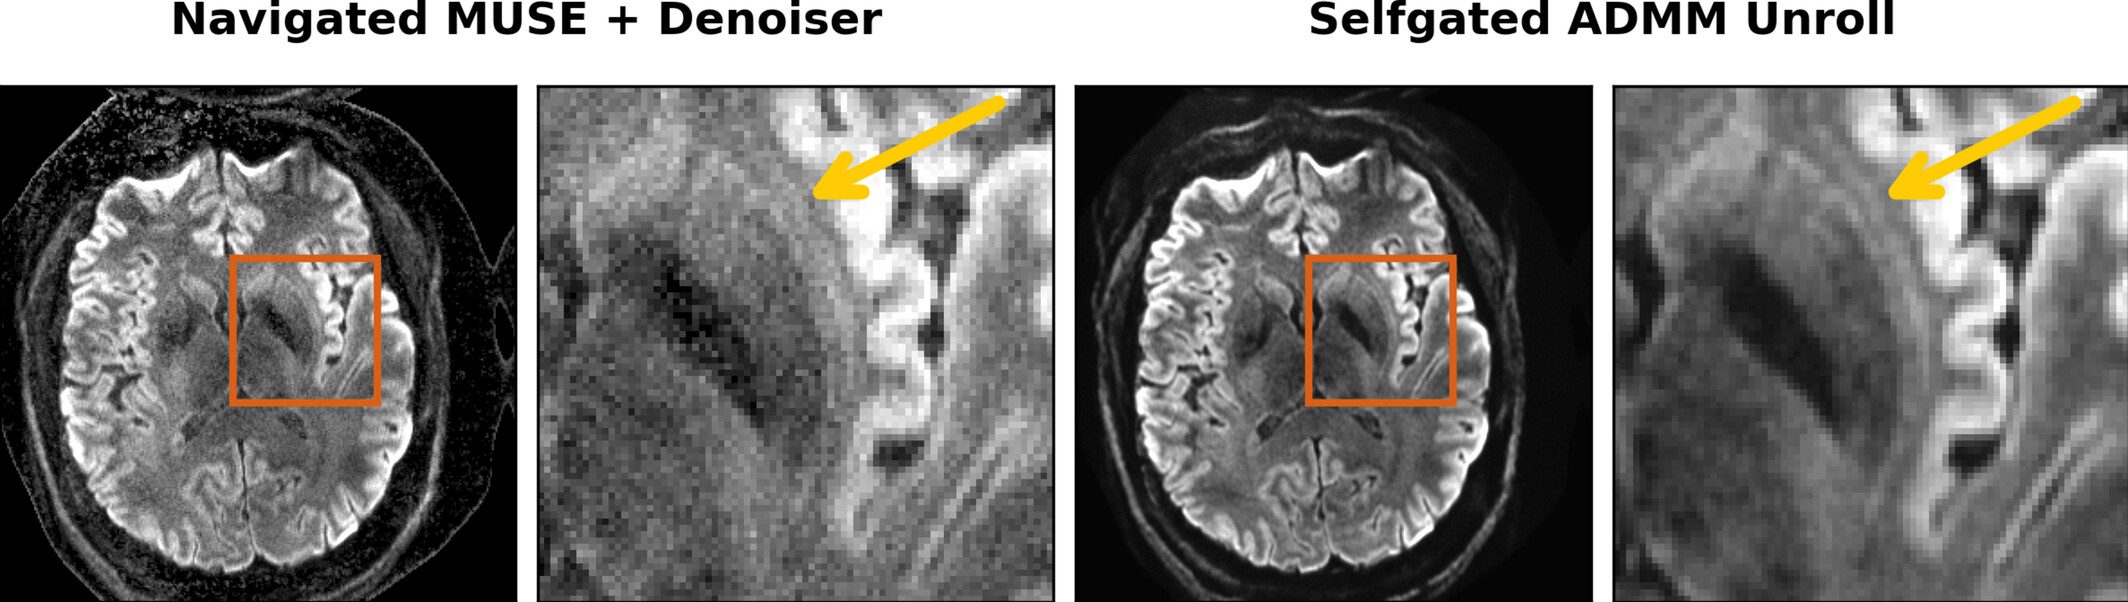

Self-Supervised ADMM Unrolling Reconstruction

ADMM Unrolling enables submillimeter DWI based on multi-band multi-shot interleaved EPI acquisition.

Example: 0.7 mm isotropic resolution DWI with the proposed self-gated ADMM unrolling enables the visualization of the tiny structure claustrum